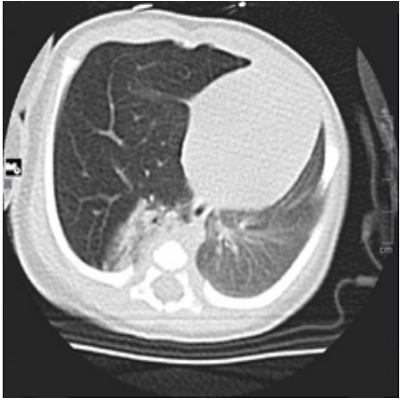

A blood test was performed revealing any disturbs in complete blood counts, as well as serum biochemistry profiles. Venous gas showed pH 7.42, pCO2 of 52 and BE 7.6. To complete the study, an echocardiography was realized, excluding congenital cardiac malformations. A chest X-ray was performed showing hyperinflation in the right upper and middle zone, with mediastinal shift to the left (Figure 1). Due to these disturbs, a chest computed tomography was realized, detecting right middle lobe hyperinflation, causing mediastinal displacement to the left (Figure 2).

Figure 2: Computed tomography showing hyperinflation of right middle lobe, with complete atelectasis of the right lower lobe and mediastinal displacement to the left.